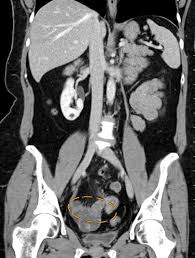

Superficial (peritoneal) disease, ovarian disease (endomet. For patients with endometriosis, the ct scan may reveal endometrial lesions on the ureters or kidneys, or on the abdominal wall. Society of radiologists in ultrasound consensus conference statement. Endometriosis is the abnormal growth of endometrial cells outside the uterus. The most common symptom is pelvic pain. Specialized radiology services in connecticut. Ct imaging findings of ruptured ovarian endometriotic cysts: Esur european society of urogenital radiology.

It is mainly found in the abdominal cavity, most commonly on the surface of the ovaries. Diagnostic radiology residents and attending radiologists are the target audience for this educational exhibit. Two radiologists performed a blinded and independent review for each ct finding. Ct imaging findings of ruptured ovarian endometriotic cysts: La mejor manera de quedar embarazada.

It is mainly found in the abdominal cavity, most commonly on the surface of the ovaries. Jan hein van waesberghe, marieke hazewinkel and milou busard. We support our ct solution with virtualcare™ remote support† and flexible support and services to meet your changing needs. Endometriosis is a full body condition in which cells similar to those in the endometrium, the layer of tissue that normally covers the inside of the uterus, grow outside the uterus. Society of radiologists in ultrasound consensus conference statement. Endometriosis is defined as the presence of endometrial tissue outside the uterine cavity. For patients with endometriosis, the ct scan may reveal endometrial lesions on the ureters or kidneys, or on the abdominal wall. Endometriosis is the abnormal growth of endometrial cells outside the uterus.

Endometriosis is a condition that must be considered in women with pelvic pain and/or infertility. Endometriosis is a full body condition in which cells similar to those in the endometrium, the layer of tissue that normally covers the inside of the uterus, grow outside the uterus. Transvaginal ultrasonography should be considered the. Journal of assisted reproduction and genetics. Ct scans can be useful for visualizing endometriosis in the abdomen, but less effective in visualizing the pelvic organs, such as the uterus. If so, the doctor may. Emphasis on the differential diagnosis with ruptured ovarian functional cysts. (from woodward dj, sohaey r, mezzetti tp: It manifests in three ways; An der linden pj (1996). Endometriosis can affect women of any age. Management of asymptomatic ovarian and other adnexal cysts imaged at us: Endometriosis is a condition that affects women.

Mayo clinic, endometriosis. radiology, endometrial cysts: We support our ct solution with virtualcare™ remote support† and flexible support and services to meet your changing needs. Journal of assisted reproduction and genetics. Ct imaging findings of ruptured ovarian endometriotic cysts: Two radiologists performed a blinded and independent review for each ct finding. Learn about treatment, causes, stages, surgery, and diagnosis. Mr imaging of malignancies arising in endometriomas and extraovarian endometriosis. Endometriosis is defined as endometrial glands and stroma that occur outside the uterine cavity. Diagnosis with mr imaging. korean journal of radiology: Endometriosis is a condition that affects women. If so, the doctor may. It is mainly found in the abdominal cavity, most commonly on the surface of the ovaries. Endometriosis is a condition where tissue similar to the lining of the womb starts to grow in other places, such as the ovaries and fallopian tubes.